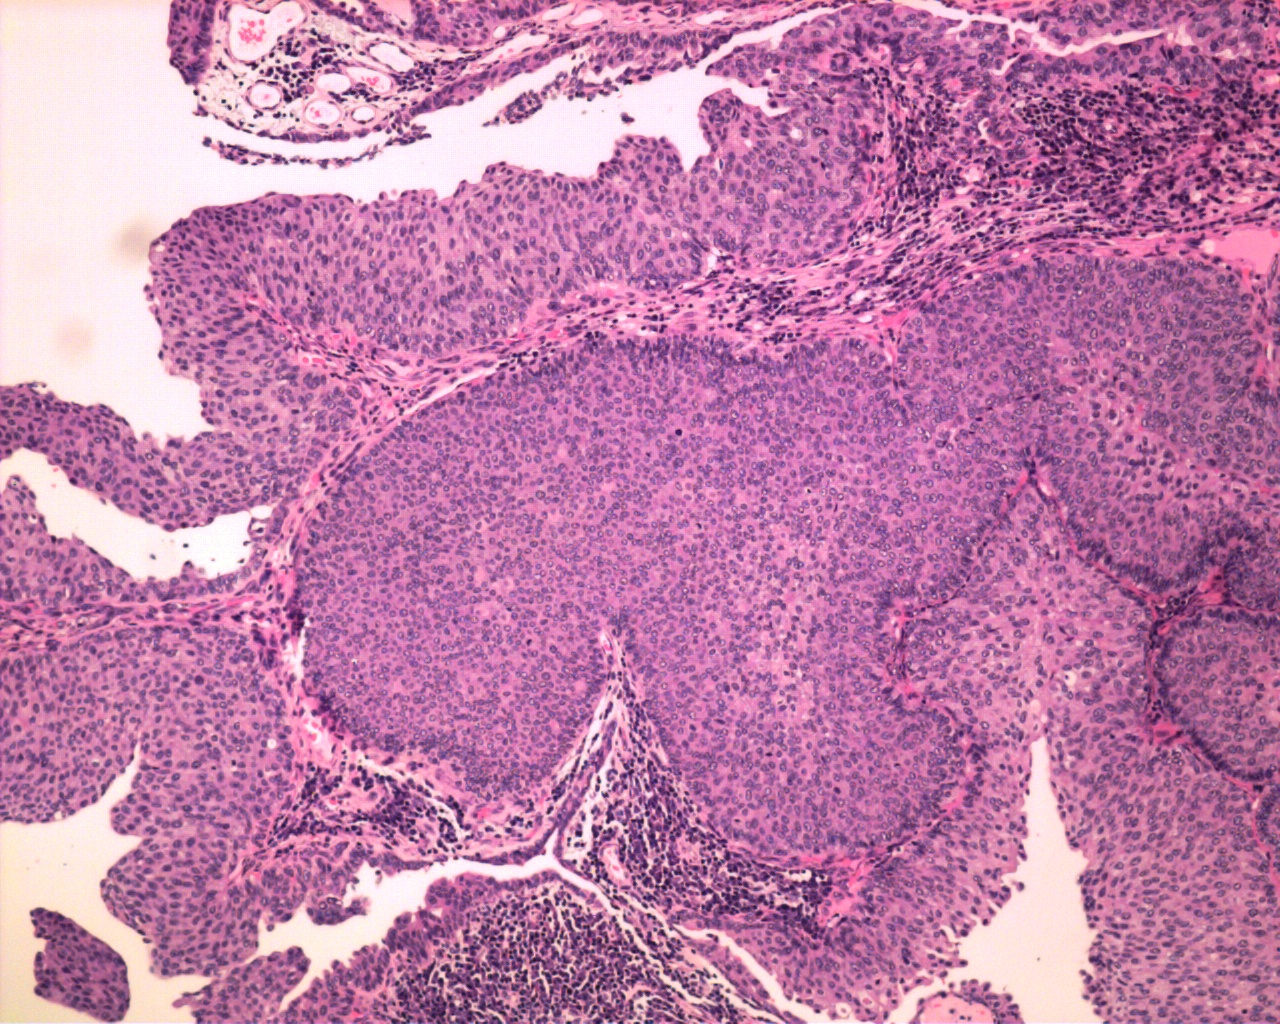

Case ID: 625

Consensus grade: Low-grade papillary urothelial carcinoma (LG-PUC)

Case description (by case creator):